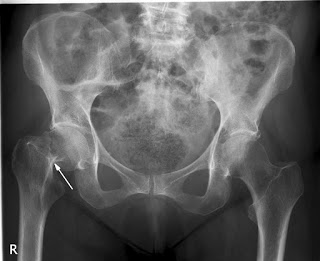

Ahora lo que debemos de saber es cuál es el eje de carga de nuestra pierna. Hay personas que tienen tendencia a tener las piernas en cruz, con las rodillas hacia dentro, muy frecuente en mujeres, son las denominadas rodillas valgas cuyo eje de carga suele coincidir en el compartimento externo de la rodilla. Otras son las que tienen las piernas arqueadas, con las rodillas hacia afuera, son las denominadas rodillas varas que suelen coincidir con un eje de carga sobre el compartimento interno, muy frecuentes en varones aunque también en mujeres mayores. Fijaros en muchos futbolistas por poner un ejemplo. Este tipo de sobrecarga interna es quizá la más frecuente. También hay muchas personas que tienen un eje de carga neutro donde se reparte el impacto de forma ordenada por los diferentes compartimentos de la rodilla. Es muy importante hacer aquí un apunte. Muchos ejes de carga que no son patológicos pueden acabar siéndolo por lesiones previas en estabilizadores de la rodilla como ligamentos o tendones.

image

A partir de ahora pensemos de forma más o menos sensata en la rueda de un coche. ¿Qué sucede si no está alineada? Pues que se gasta más en un lado que en otro deteriorándose al final en su conjunto. Nuestro caucho podría representarse por el cartílago de la rodilla que tapiza la superficie ósea, pero además tenemos unas estructuras protectoras que son los meniscos. Imaginaros ahora el trabajo y los traumatismos continuos que sufre un menisco con un eje de carga desalineado. Así, es frecuente ver a muchos pacientes de mediana edad (40-60) con dolor en la parte lateral o medial de la rodilla, sin un antecedente claro de traumatismo o golpe.

Hoy nos centramos en esos casos de sobrecarga medial, porque tras realizarse la resonancia aparecen con una rotura degenerativa meniscal e incluso extrusión (que se sale de su sitio hacia afuera) del menisco porque está ¡muy apretado! Es que es lógico ¿verdad? Además el fracaso meniscal suele acompañarse de cambios degenerativos en cartílago, es decir desgaste o lo que es lo mismo, artrosis del compartimento afectado, en este caso medial. Muchas de estas rodillas acaban fracasando ademas, en los demás compartimentos. Ojo, no siempre todo coincide de esta manera pero como base nos sirve para entender el proceso.